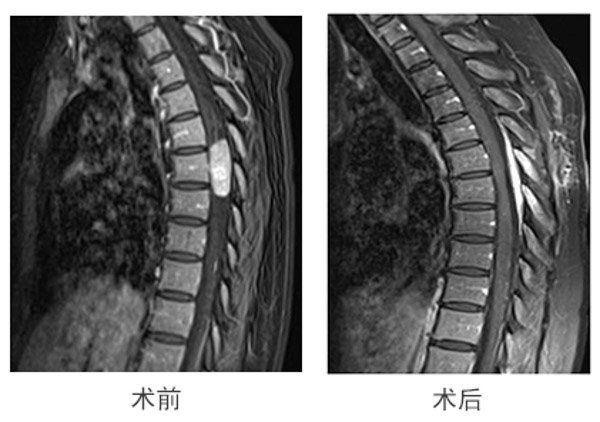

33岁的侯女士因为胸背部疼痛1年余,双下肢麻木乏力、行走不稳半年来到柳州市人民医院就诊,经检查发现胸7椎体水平椎管肿瘤,神经外科治疗团队也是根据患者的自身特点制定了手术方案并予以实施。

在术中电生理监测下,通过神经内镜从侧方肌间隙微通道入路,精准切除了肿瘤,仅仅留下了4cm的手术切口,这种手术方式肌肉损伤小,仅磨除小部分椎板,棘突及韧带保留,降低了患者术后椎柱失稳的风险,且无需内固定。术后第二天患者便可下床,出院时能自行行走。